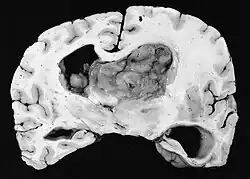

Photograph of a brain section containing a subependymal giant cell astrocytoma

A NIH Consensus Conference report in 1999 recommends that any SEGA that is growing or causing symptoms should be surgically removed.[2] Tumors are also removed in cases where a patient is suffering from a high seizure burden.[1] If a tumor is rapidly growing or causing symptoms of hydrocephalus, deferring surgery may lead to vision loss, need for ventricular shunt, and ultimately death. Total removal of the tumor is curative.